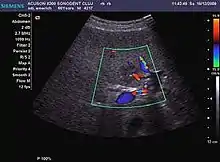

Hepatocellular carcinoma (HCC)

It is the most common liver malignancy. It develops secondary to cirrhosis therefore, ultrasound examination every 6 months combined with alpha fetoprotein (AFP) determination is an effective method for early detection and treatment monitoring for this type of tumor . Clinically, HCC overlaps with advanced liver cirrhosis (long evolution, repeated vascular and parenchymal decompensation, sometimes bleeding due to variceal leakage) in addition to accelerated weight loss in the recent past and lack of appetite.

HCC appearance on 2D ultrasound is that of a solid tumor, with imprecise delineation, with heterogeneous structure, uni- or multilocular (encephaloid form). An "infiltrative" type is also described which is difficult to discriminate from liver nodular reconstruction in cirrhosis. Typically HCC invades liver vessels, primarily the portal veins but also the hepatic veins . Doppler examination detects a high speed arterial flow and low impedance index (correlated with described changes in tumor angiogenesis). The spatial distribution of the vessels is irregular, disordered. CEUS examination shows hyperenhancement of the lesion during the arterial phase. During the portal venous phase there is a specific "wash out" of ultrasound contrast agent (UCA) and the tumor appears hypoechoic during the late phase. Poorly differentiated tumors may have a stronger wash out leading to an isoechoic appearance to the liver parenchyma during portal venous phase. This appearance was found in approx. 30% of cases. The described changes have diagnostic value in liver nodules larger than 2 cm.